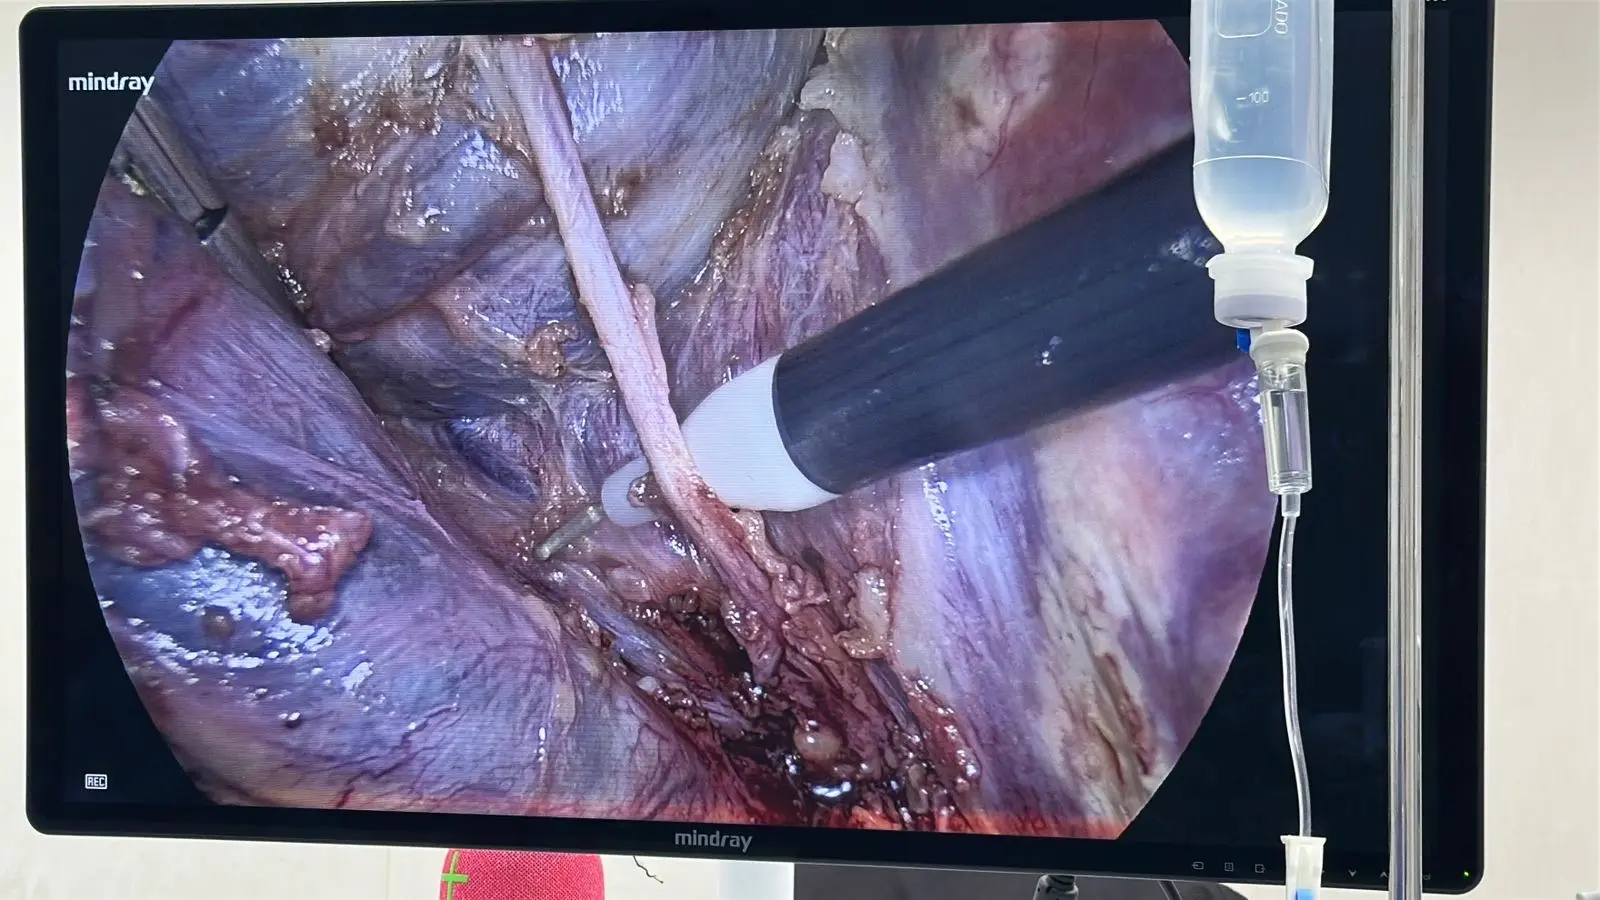

El Dr. Mario Ruvalcaba realiza la colecistectomía laparoscópica en Mérida a través de 3 a 4 pequeñas incisiones de entre 5 y 12 mm bajo anestesia general. La cirugía dura entre 45 minutos y 1.5 horas: se introduce una cámara de alta definición y los instrumentos quirúrgicos para identificar, clipar y extirpar la vesícula biliar con precisión, extrayéndola dentro de una bolsa endoscópica. En la gran mayoría de los casos el paciente se va a casa el mismo día o al día siguiente, con mínimo dolor manejable con analgésicos orales.